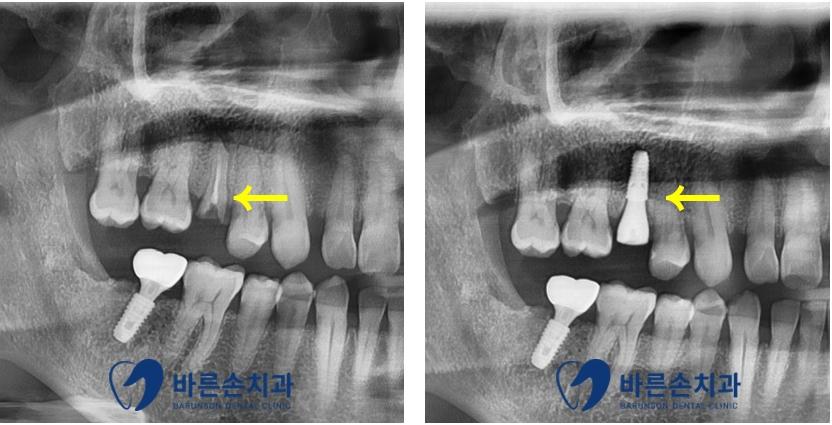

치아가 부러진 후 찍은 엑스레이 사진과 육안 사진입니다

엑스레이 상 치아의 뿌리는 잘 유지되고 있지만

육안상 치아의 머리 부분이 모두 손실되어 있는 것이 보입니다

이런 경우 치료할 수 있는 치아의 머리 부분이 부족하여

치료를 진행할 수 없기에

아쉽지만 발치 후 임플란트 수술을 하기로 하였습니다